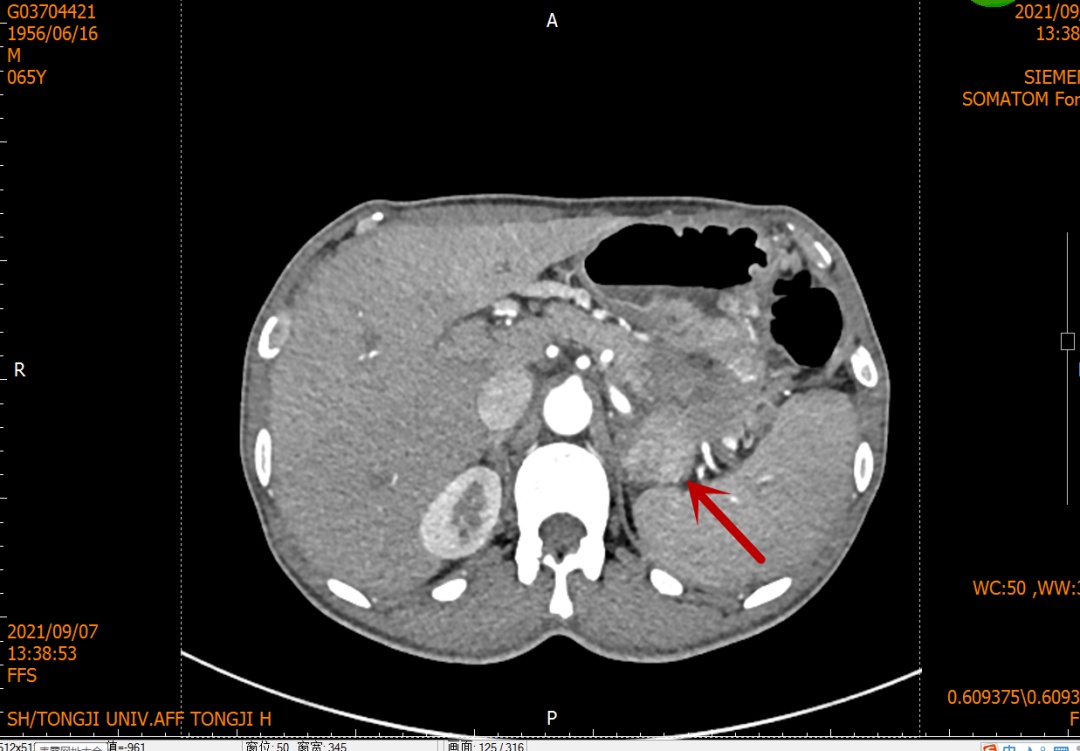

患者为一位60多岁男性,因“纳差,消瘦三月余”在当地医院行胃镜检查提示:胃底、贲门肿瘤;CT检查发现肿瘤体积较大,侵犯胰腺及脾门可能。患者家属慕名来到同济医院找到施宝民主任就诊。

施主任接诊病人后,尽快安排患者住院并完善术前检查。增强CT等影像显示胃部肿瘤体积较大,浸润范围广,位于胃底、胃体直到贲门,向后已经侵犯脾动静脉脉及脾门,与胰腺体尾部浸润成一团。单纯全胃切除术不能完整切除肿瘤,而必须联合三脏器切除(全胃+脾脏+胰腺体尾部)做整块切除。但手术难度大,创伤大,给医患双方都是巨大挑战。开腹手术切口长、创伤大,腹腔镜腔镜手术的切口小、创伤相对较小,但对手术团队腹腔镜外科技术要求更高。最终结合患者一般情况,经全科医生讨论后,决定实施腹腔镜辅助下全胃切除术+脾脏切除术+胰体尾部切除术+淋巴结清扫术。在麻醉科韩松副主任医师的精准麻醉和通力配合下,施宝民主任带领团队成员林锐、季堃主治医师用时4个多小时,顺利完成了手术。